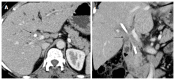

Hilar cholangiocarcinoma is a common malignant tumor of the biliary tree. It has poor prognosis with very low 5-year survival rates. Various imaging modalities are available for detection and staging of the hilar cholangiocarcinoma. Although ultrasonography is the initial investigation of choice, imaging with contrast enhanced computed tomography scan or magnetic resonance imaging is needed prior to management. Surgery is curative wherever possible. Radiological interventions play a role in operable patients in the form of biliary drainage and/or portal vein embolization. In inoperable cases, palliative interventions include biliary drainage, biliary stenting and intra-biliary palliative treatment techniques. Complete knowledge of application of various imaging modalities available and about the possible radiological interventions is important for a radiologist to play a critical role in appropriate management of such patients.We review the various imaging techniques and appearances of hilar cholangiocarcinoma and the possible radiological interventions.